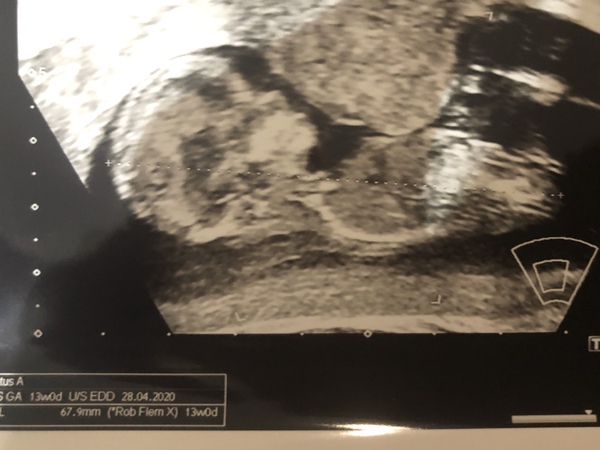

May2311 · 23/10/2019 10:14

Hi everyone - Baby looking healthy & perfect. Heart beating away nicely ❤️ We woke baby up so it started stretching legs and rubbing it’s face hence it’s little devil horn on its head( it’s actually it’s hand) 😂 EDD: 14 May 2020 which is what I thought I was at but 12 days later than midwife who dated from LMP. All in all absolutely perfect being able to see our little bambino ❤️❤️❤️💕💕💕 Good Luck to everyone else who is having A scan today. @helensss hope today goes quickly for you!!!

@may2311 aww congrats 💕 I had to run around the carpark and jump up and down for 10 mins because baby was lying on its stomach 😂 it worked though! Sent her to sleep and then they could take the nuchal measurements